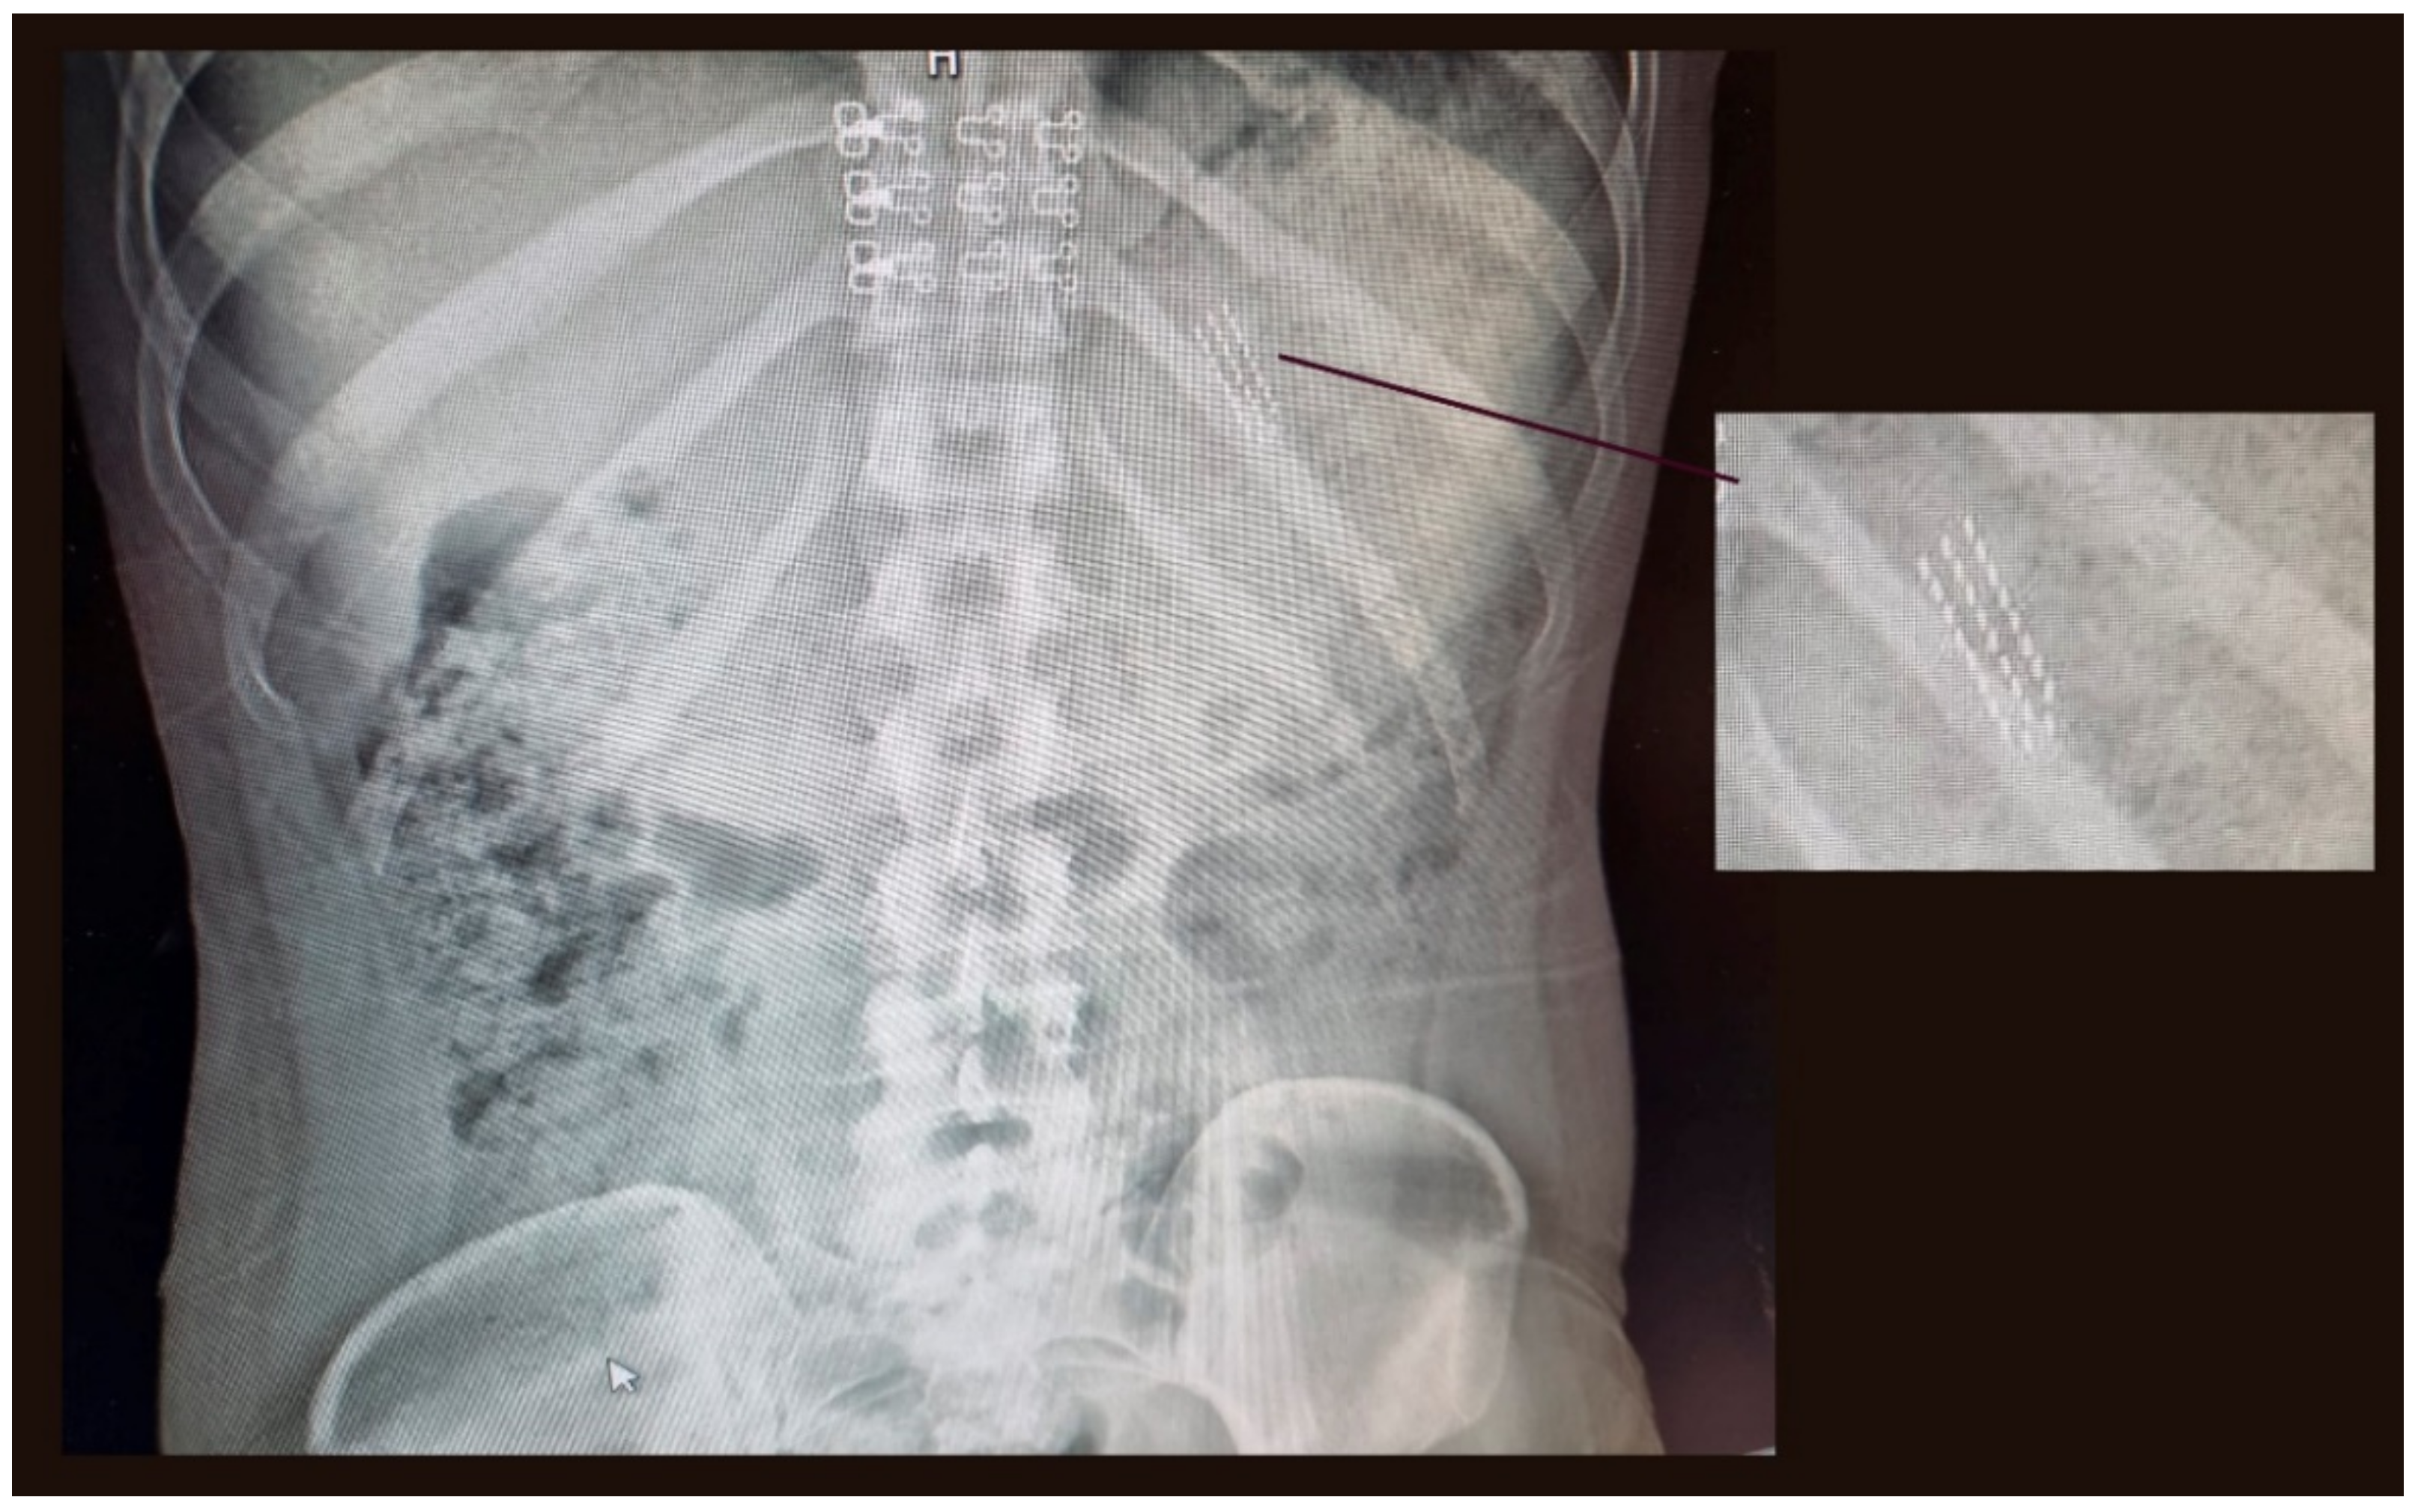

2. Case Report